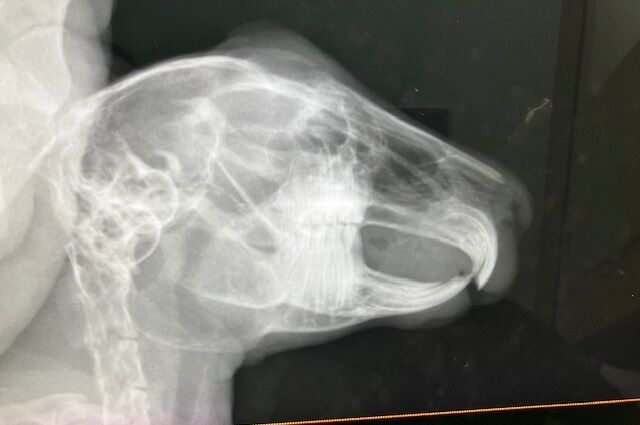

1月前半、まだ画像に納める余裕がある(^^;)